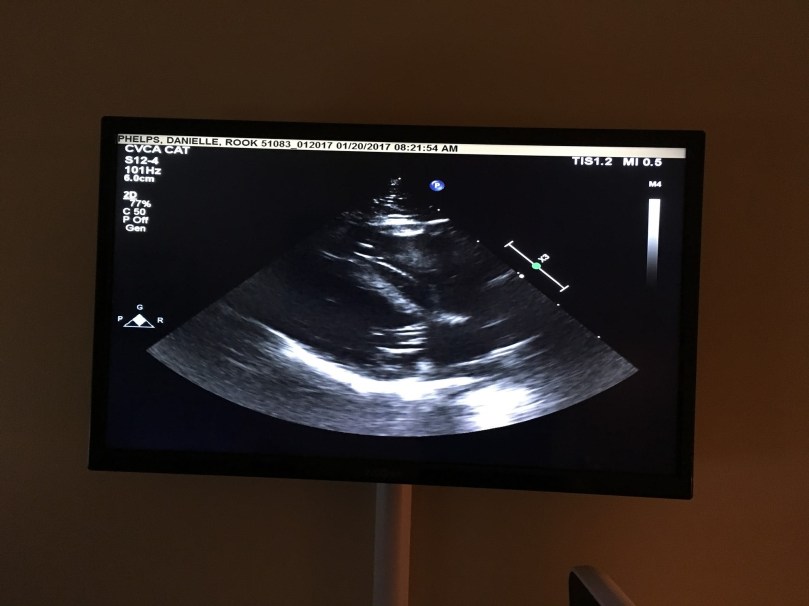

Let’s be honest, I don’t know what the above photo is supposed to mean, BUT the results of the ultrasound diagnosed Rook with unclassified cardiomyopathy. While some classes of cardiomyopathy involve the thickening of the heart lining, and others the thinning of the heart lining, Rook has “mild concentric hypertrophy of the interventricular septum and thinning of left ventricular free wall,” so both. He didn’t fit in a perfect category of heart disease, thus unclassified. Oh Rook, even in health you have to be an odd one.

This was the description given in his medical notes:

This changes to the left ventricular heart muscle decreases how well the heart can relax, which will over time lead to enlargement of the left atrium and left auricle. With chronic elevations in left atrial pressure the pressure in the pulmonary veins increases causing fluid to leak from the vessels into the lung tissue. This is called congestive heart failure.